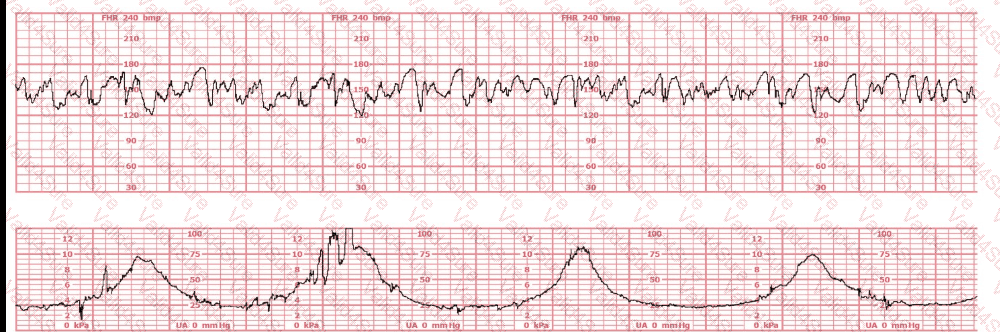

The baseline fetal heart rate in this tracing is:

A.

155 beats per minute

B.

Indeterminate

C.

Tachycardia

The fetal heart rate tracing shown represents

category I

category II

category III